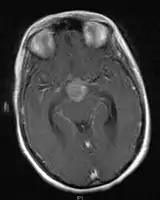

- Mainly located in midline structures, suprasellar region or pineal gland, also basal ganglia and hypothalamus

- Suprasellar Germinoma